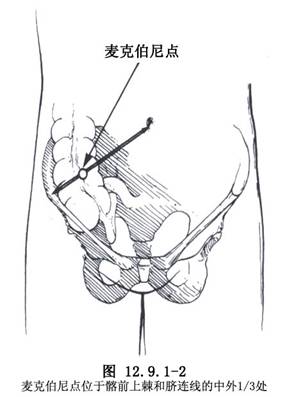

⑴右下腹斜切口(mc burney):右下腹斜切口,即麥克伯尼(Mc Burney’s)切口。經臍孔與右髂前上棘連線外中1/3交點(麥克伯尼點)做與該連線垂直的皮膚切口(圖12.9.1-2,12.9.1-3A)。此切口肌肉交叉,癒合較牢固,不易形成切口疝;且距闌尾較近,便於尋找。切口一般長5~7cm。對診斷有把握的病人多采用此切口。